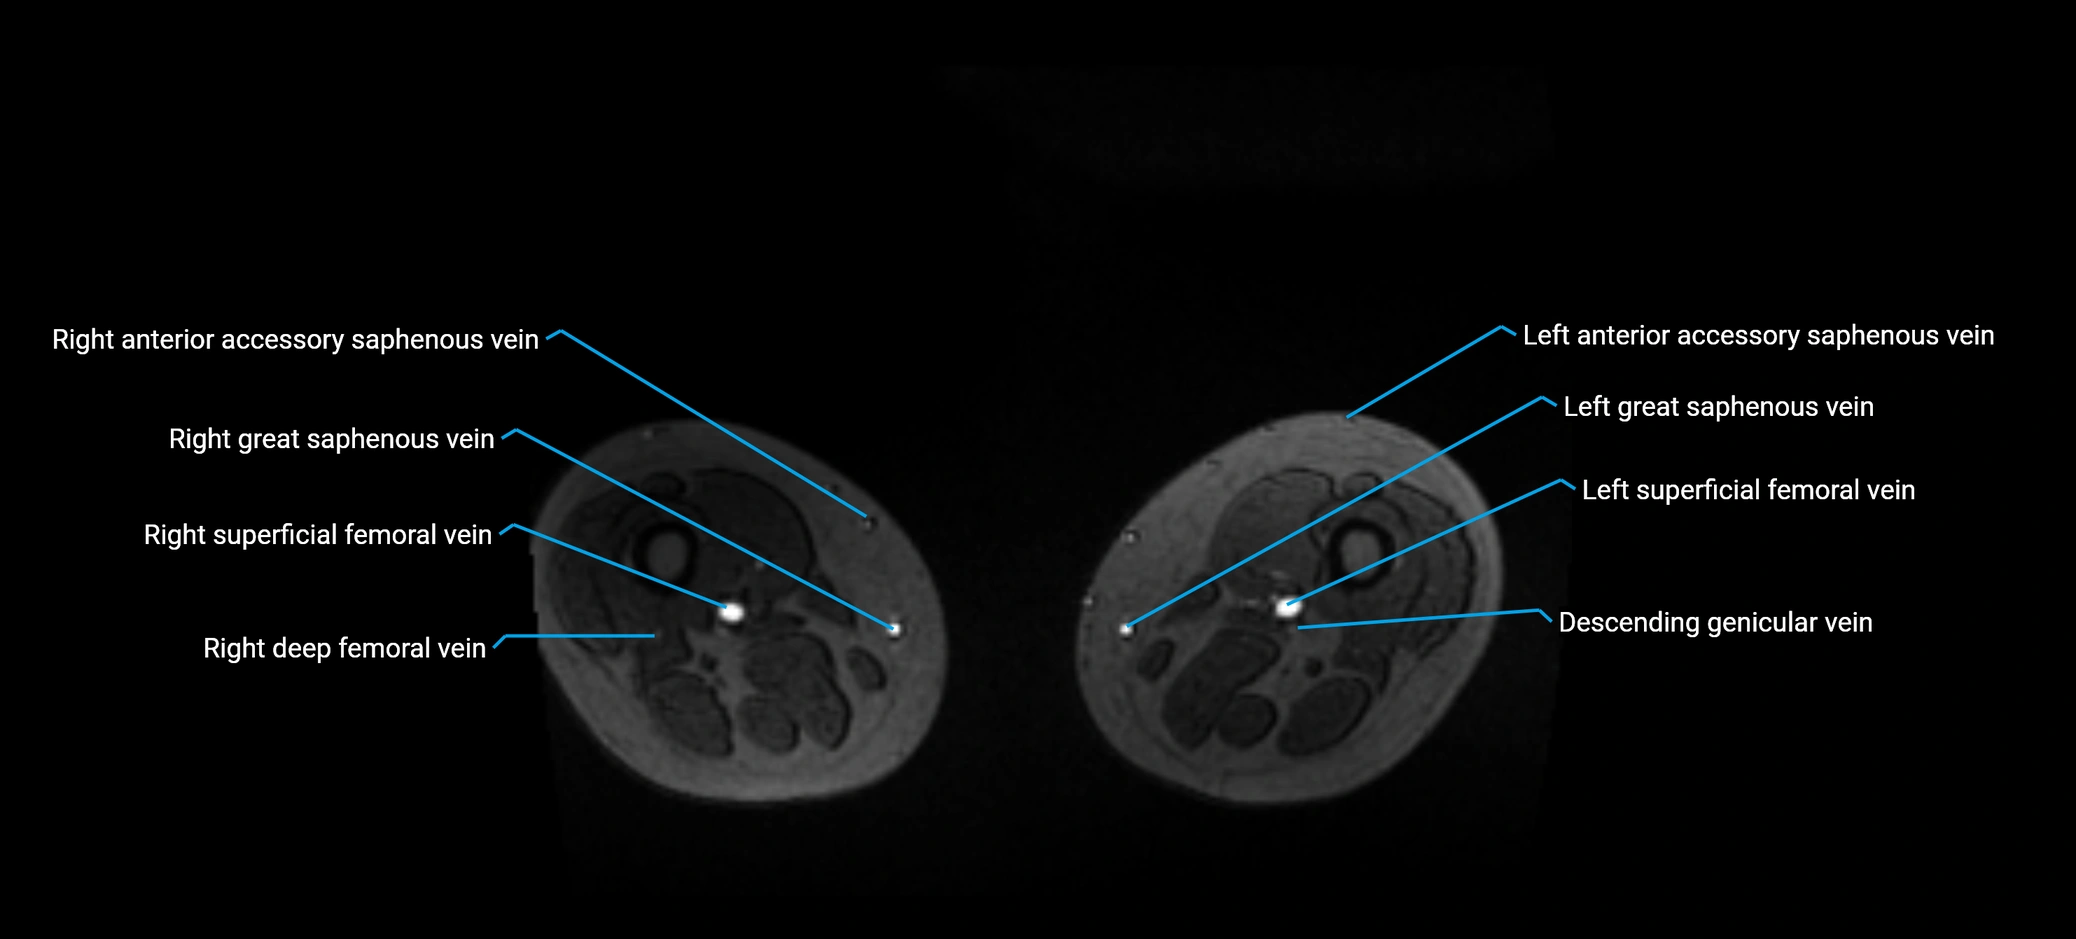

MRI image

image